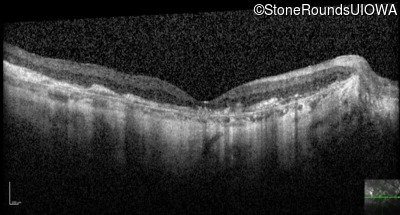

Optical Coherence Tomography - Left - 20/160 -1

Exemplar / OCT Stack

OCT Stack